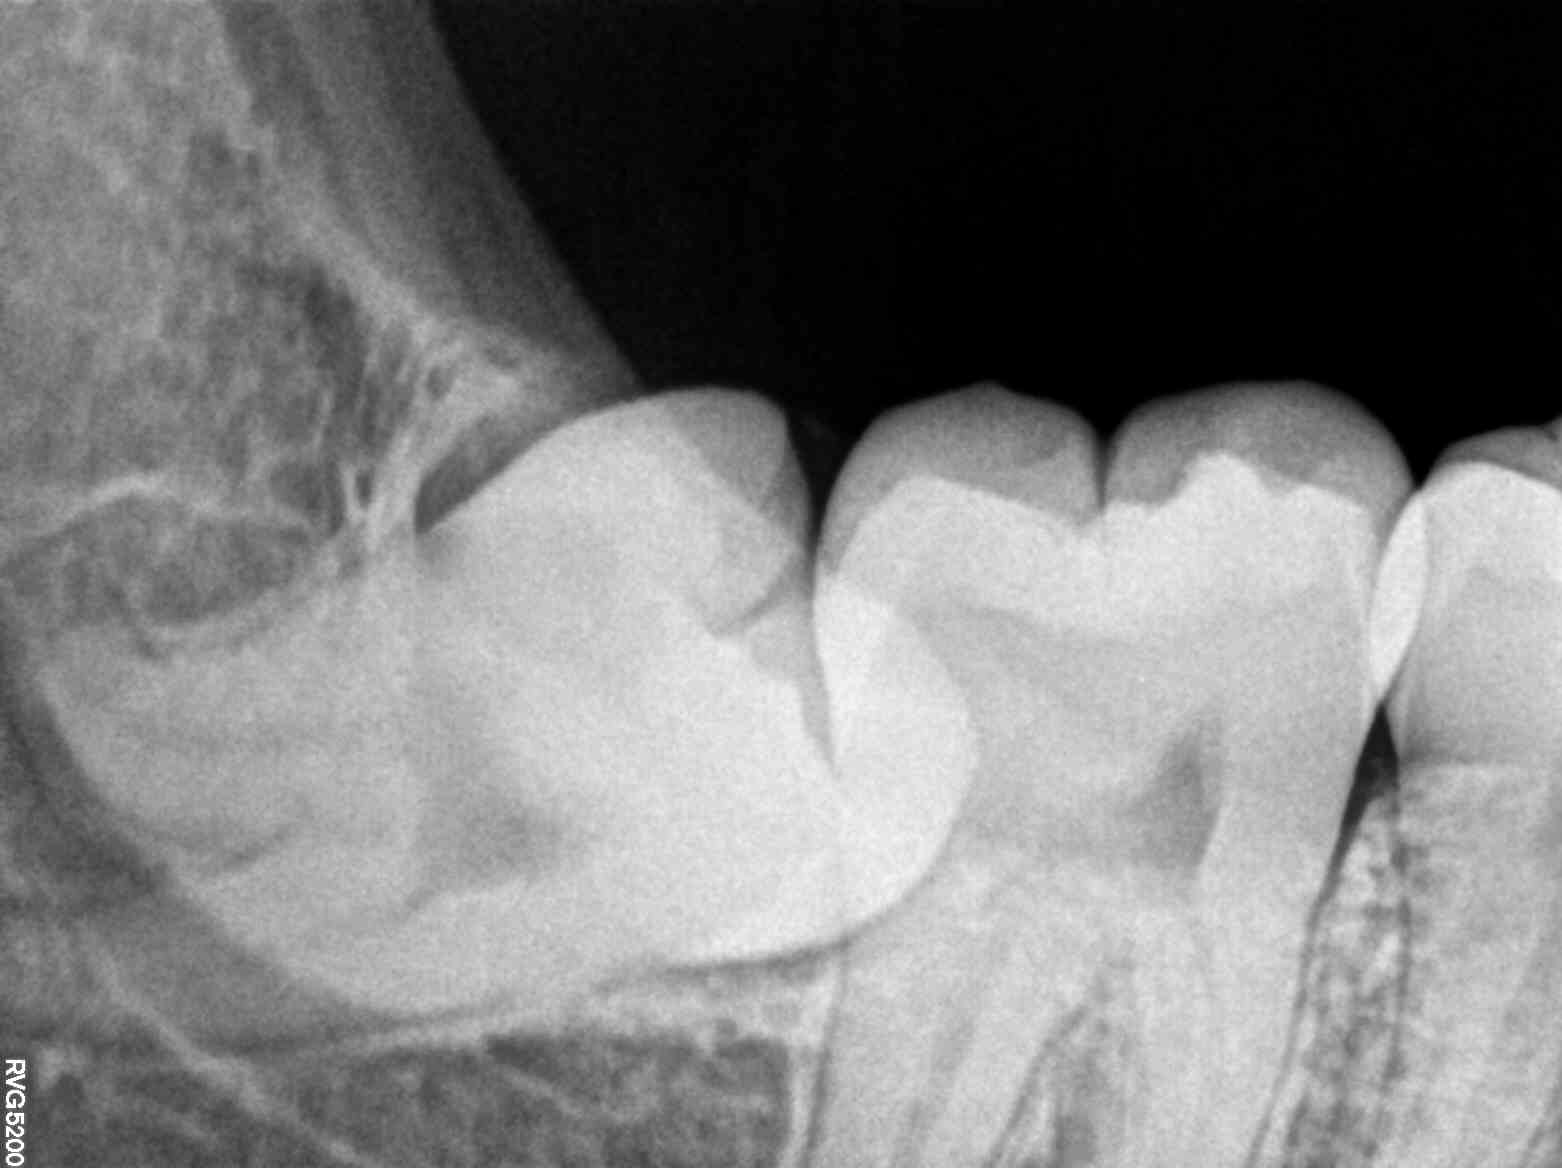

The traditional idea of dental care often evokes images of discomfort, long hours, and uncertainty. This is where digital X-rays come into play, revolutionizing how dental issues are diagnosed and treated. For individuals like Meera, who dread the idea of spending long hours in a dentist’s chair, digital X-rays offer a practical solution by significantly reducing examination time and improving diagnostic accuracy.

Upon entering the clinic, Meera was greeted by a warm, professional atmosphere that eased her anxiety. The dentist, Dr. Raghav, quickly identified her concern and suggested using digital X-rays for a comprehensive examination. As Meera sat in the chair, Dr. Raghav explained how digital X-rays work—capturing detailed images of her teeth and gums with minimal radiation exposure. This technology allowed for a quick, painless experience while providing a clear view of potential issues that could be missed with the naked eye.

Digital X-rays are a boon for individuals like Meera, who seek comfort and efficiency in their dental visits. These X-rays offer a distinct advantage by providing immediate results, enabling dentists to swiftly diagnose and plan the necessary treatment. For Meera, who values her time immensely, this was a revelation. She no longer had to juggle multiple appointments or deal with uncertainties; the solution was quick and precise.